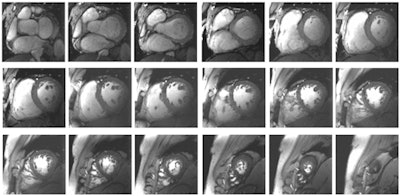

The high-resolution (1 x 1 x 2.5-mm) dataset of the heart was acquired at 7 tesla from a healthy subject. The images show whole heart coverage from the apex to the base of the heart. All images are courtesy of Thoralf Niendorf, PhD."This will only happen if we recognize that moving into ultrahigh fields is more than just a matter of buying magnets and installing them and trying to operate them in core facilities, armed with the concepts that have guided discovery in the lower fields," the authors noted (Circ Cardiovasc Imaging, 13 June 2017).